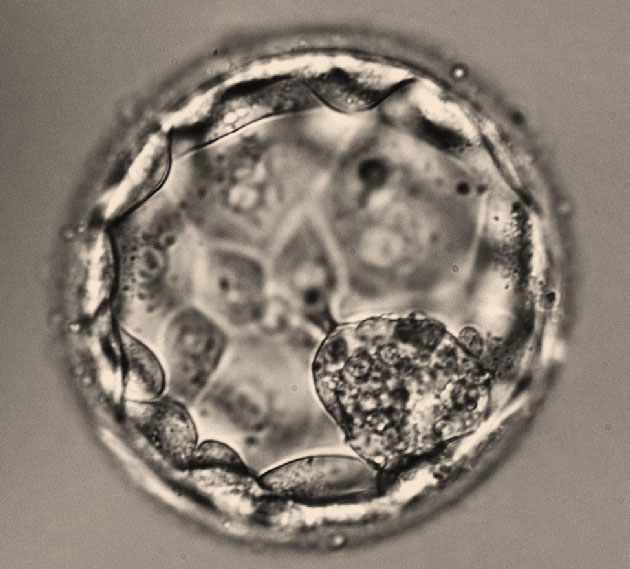

Les microARNs dans le milieu de culture des blastocystes sont dérivés des cellules du trophectoderme et peuvent être étudiés afin d’évaluer la compétence de l’embryon humain à s’implanter

Dr Elodie Scalici Montpellier

Le sécrétome des blastocystes contient des microARNs issus du trophectoderme, pouvant être utiles à l’évaluation de leur potentiel d’implantation. Les microARNs correspondent à de petites séquences d’ARN simple brin non codantes d’environ 22 nucléotides de long. Ils sont à l’origine d’une régulation dite « post-transcriptionnelle » qui consiste à mettre sous silence l’expression...